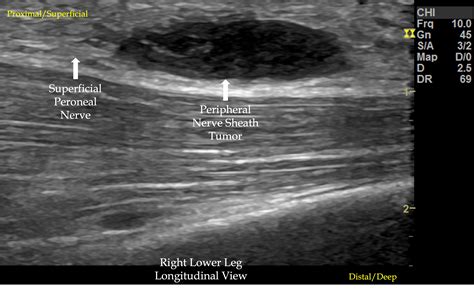

• nerve sheath tumor ultrasound